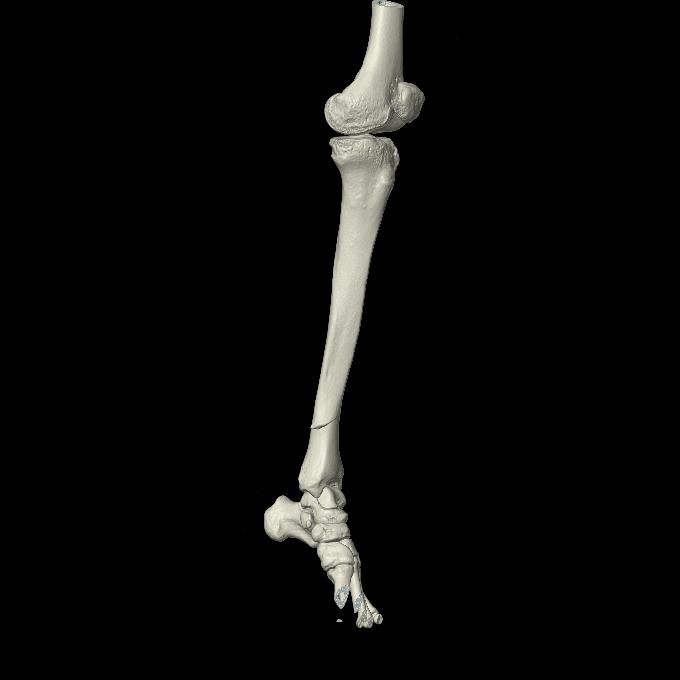

102803 1/12(キウスなし) 1/27 左下腿 4R 30歳女性 左脛骨軸内釘